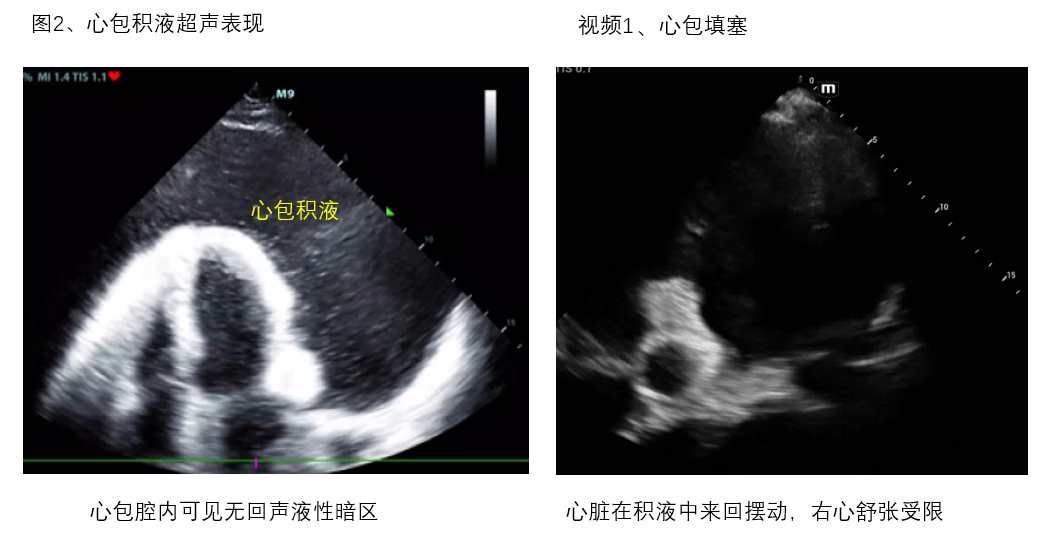

A、心包腔 观察有无心包积液,及其引起右心舒张受限、心包填塞导致循环衰竭的超声证据(图2、视频1)。此外,对于心包积液者,需谨慎观察有无主动脉增宽、漂浮的内膜片等夹层证据及心室壁不连续、异常血流通道等心脏破裂超声证据,区别主动脉夹层破裂、心脏破裂等原因引起的心包积血(图3、视频2)。

(图2、视频1)

视频1-心包填塞